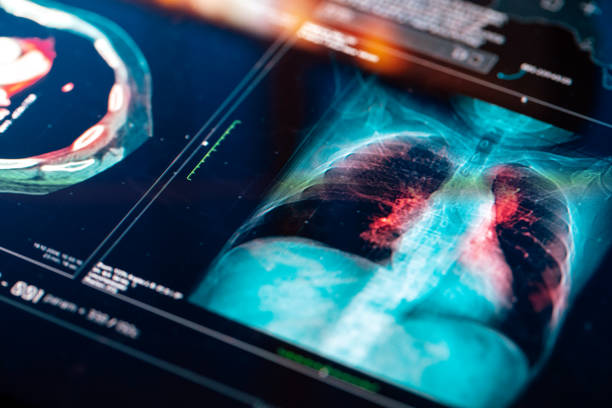

또한, 정기적인 건강 검진, 특히 엑스레이 등의 폐 검사를 받는 것도 중요합니다. 호흡기 증상이나 다른 이상 증상이 있을 경우, 빨리 의료 전문가와 상담하여 필요한 검사를 받는 것이 생명을 지킬 수 있는 선택일 수 있습니다.

폐암은 폐에서 생기는 악성 종양으로, 결절이라고도 불립니다.

이러한 결절은 폐 내에 작은 덩어리 혹은 종양으로 나타날 수 있으며, 그 중에서도 양성과 악성 종양이 구분됩니다.

악성 종양은 일반적으로 암이라고 알려져 있으며, 폐암이라고도 불립니다.